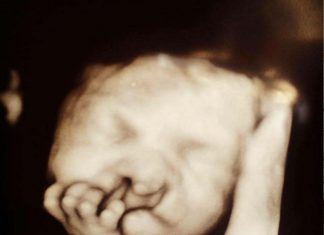

Pais se recusam a abortar – 3 meses depois, a mãe...

Heller e Chris Eidan esperavam seu primeiro filho com a alegria que é comum a pais de primeira viagem. Os dois escolheram o nome,...